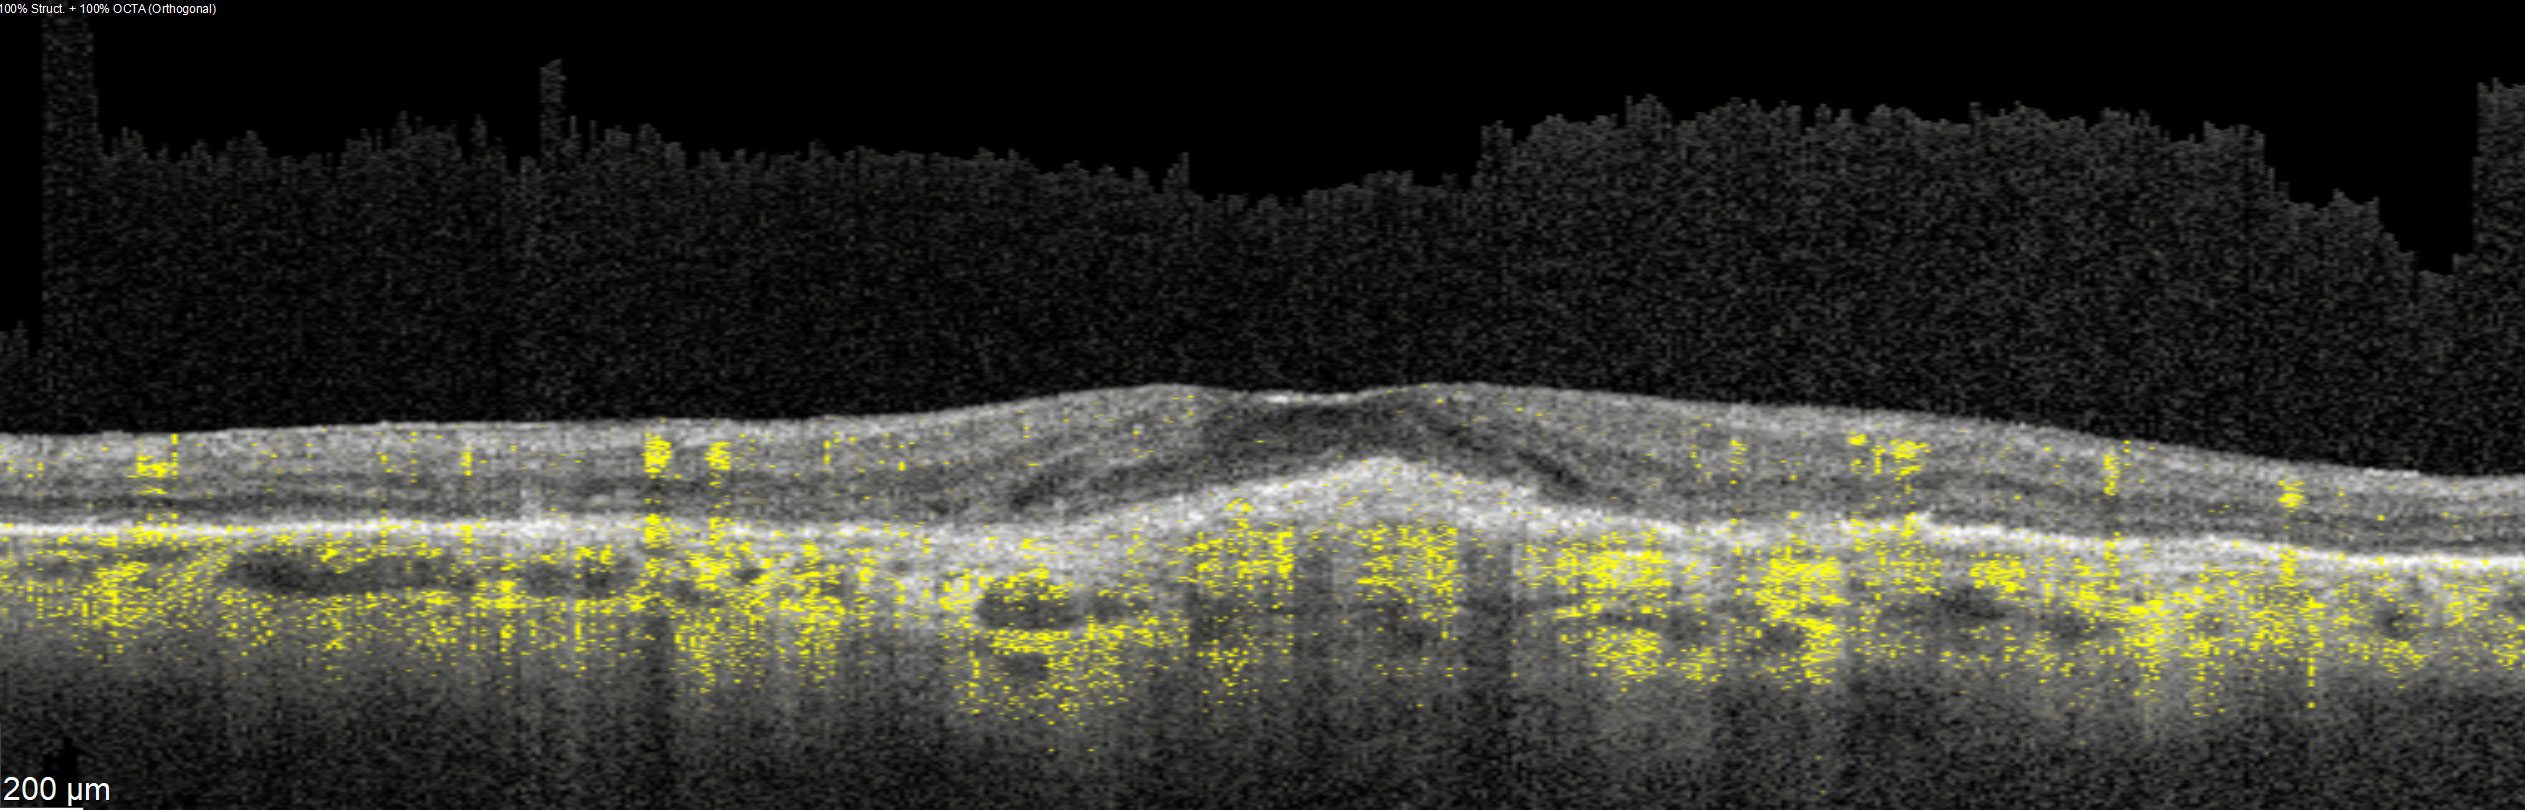

Offering the ideal speed-quality ratio for OCTA, 125 kHz allows you to increase your throughput without any clinically relevant loss in image quality in comparison to the current 85 kHz scan speed. The fast acquisition of images allows for visualization of flow, even in miniscule vessels, while minimizing artefacts, resulting in sharp and detailed images of the capillary network. Additionally, you can decrease chair time when you speed up acquisition with the Glaucoma Module Premium Edition in your glaucoma workflow, if applicable.

SPECTRALIS with SHIFT technology and 125 kHz scan speed empowers you to offer customized diagnostic OCTA imaging of both the retina and the optic nerve head to meet the needs of each individual patient – or adjust to 85 kHz if your patient’s condition requires longer light exposure.

125 kHz – A fast scan speed for improved workflow and high OCTA image quality.